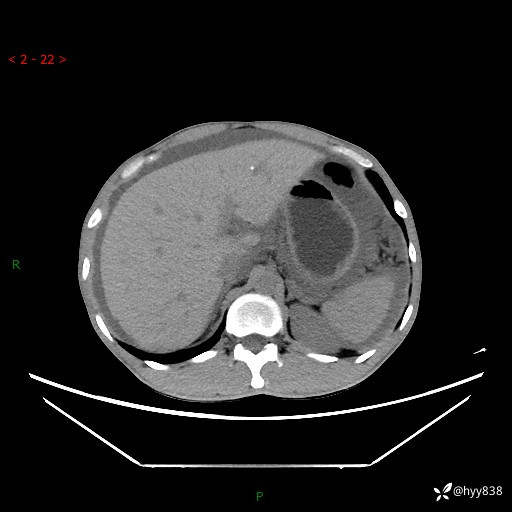

现病史:患者10天前无明显诱因出现腹部胀痛不适,无畏寒发热,无胸痛胸闷,无心慌气短,无恶心呕吐,无腹泻及黑便,无粘液血便及里急后重等症状,4天前在当地县人民医院就诊,行腹部CT示:下腹部占位性病变,腹腔及盆腔积液;今患者为求进一步诊治来我院治疗,门诊以“腹水”收治入院。 发病以来,精神饮食可,大小便正常,体重体力无明显变化。

腹部CT平扫+增强